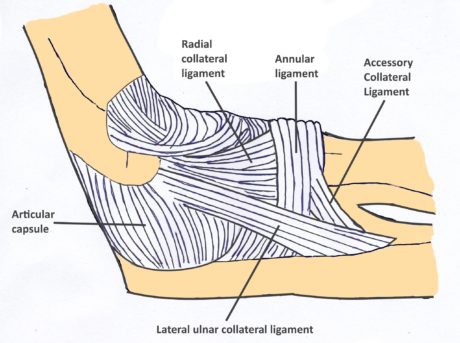

Albuen er det led i kroppen, der næst efter skulderen oftest går af led. PLRI er den mest almindelige form for albueinstabilitet som følge af en overrivning af det laterale kollaterale ligamentkompleks. Dette fører til posterolateral rotatorisk subluksation af ulna og radius.

Albuen er det led i kroppen, der næst efter skulderen oftest går af led. PLRI er den mest almindelige form for albueinstabilitet som følge af en overrivning af det laterale kollaterale ligamentkompleks. Dette fører til posterolateral rotatorisk subluksation af ulna og radius.Det opstår typisk som følge af et fald på den udstrakte hånd, hvilket genererer en aksial belastning, valguskraft og en ekstern rotationsbevægelse omkring underarmen i forhold til overarmsbenet.

Det får det radiale hoved og den proksimale ulna til at subluksere posterolateralt væk fra humerus på en roterende måde, der løsner eller river det laterale kollaterale ligamentkompleks (LCL)(Camp et al. 2017).